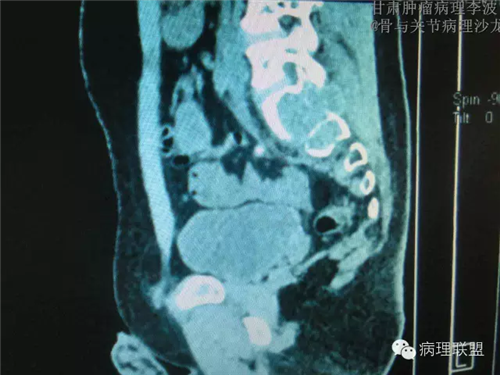

M/14 骶骨骨肉瘤-张惠箴讲解

病例由甘肃肿瘤病理 李波 提供,致谢。